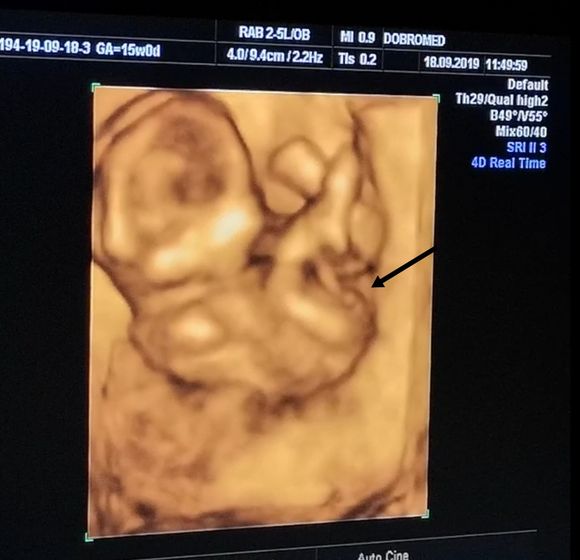

14 недель и 7 дней, нам врач сказала что точно видно мошонку и это мальчик… но я не уверена ? у него пуповина между ног была, короче я запуталась.

На 1 скрининге нам предположили что будет девочка, а тут сюрприз вырос....... Может всё таки пуповина? ?

Видно что мальчик, а в целом какая разница кто, главное что бы зборовый был ребенок

врачам стоит доверять)

Ага. Видно чётко. Поздравляю с мальчиком ???